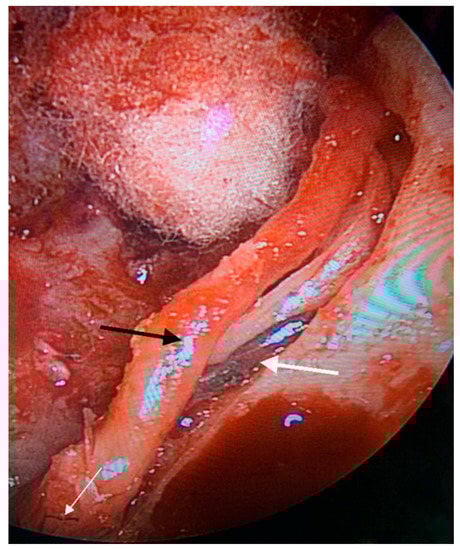

2. Case Presentation